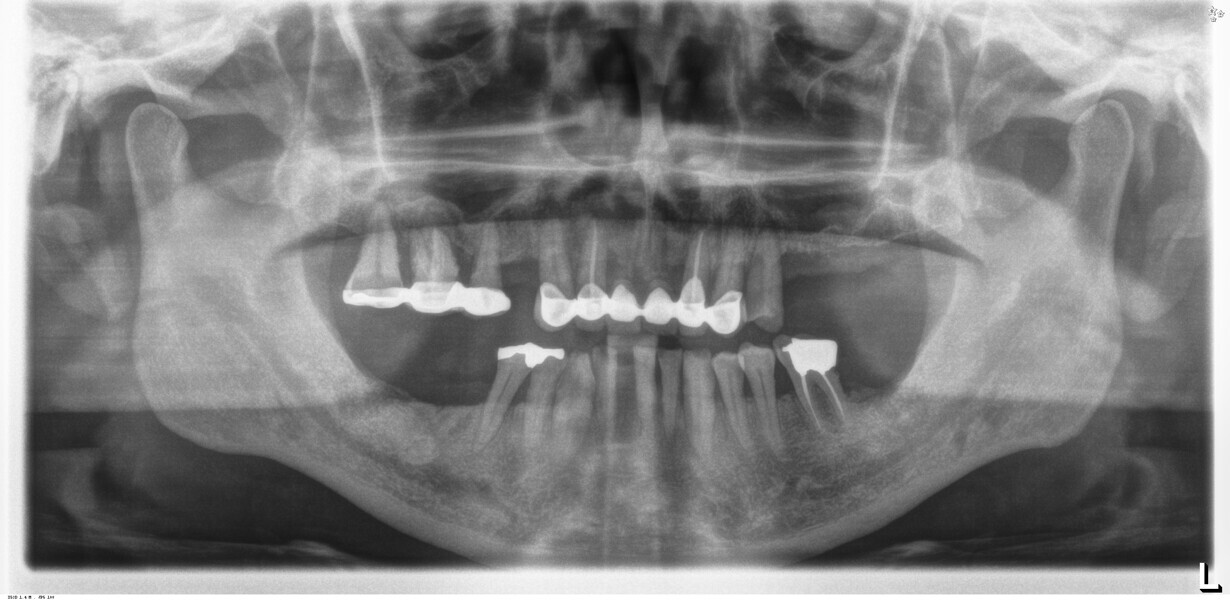

Compromised maxillary dentition treated with Straumann Pro Arch and a digital workflow